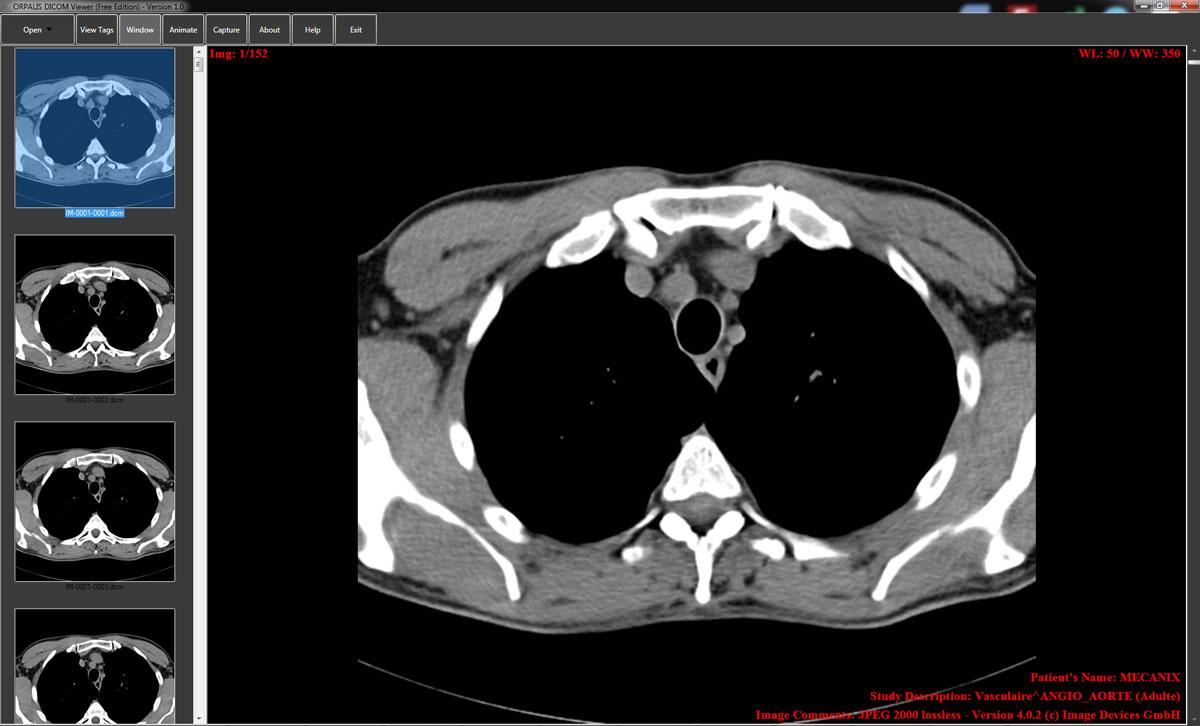

You can’t write an accurate report if you can’t see the details. A robust DICOM viewer is as essential as a sharp microscope is to a pathologist.

Modern viewers go beyond simple display. They offer features that directly contribute to diagnostic confidence. Look for tools like adjustable windowing and leveling to bring out subtle contrast differences, zoom functions for a closer look at fine details, and side-by-side comparison for tracking changes over time. These technical capabilities are your first line of defense against perceptual errors.

A powerful viewer transforms a static image into a dynamic dataset you can explore. Don’t settle for a viewer that feels clunky or limited. The right tool should feel like an extension of your own vision, helping you isolate and interrogate findings with precision.